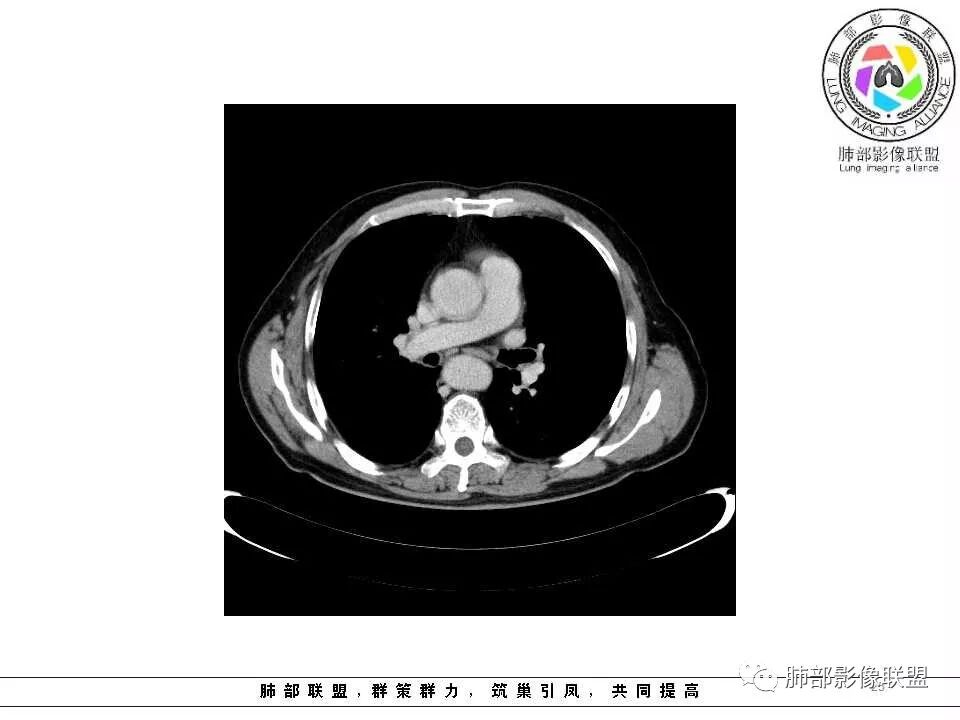

纵隔窗上似乎结节内可见点状高密度影,同时没有明显肿大淋巴结

肺气肿背景,2016年左肺上叶上舌段见微结节,2017年5月左肺结节增大,密度均匀,边缘光滑锐利,与邻近血管关系密切,血管贴壁走行,外侧见尖状突起,下舌段片状影,沿着支气管走行,内有粘液栓,考虑鳞癌,鉴别小细胞肺癌。

肺气肿背景,2016年左肺上叶上舌段见微结节,一年后左肺结节增大,密度均匀,边缘光滑、膨隆,似见小分叶,下舌段片状影,沿着支气管走行,内,老年患者,咯血1月。考虑恶性病变并阻塞性肺炎,鳞癌?注意鉴别结核。

左肺上叶舌段支气管管壁略增厚 间隔一年 管壁增厚明显 向腔外突出形成结节 管腔闭塞 远端片状及斑片影 纵隔淋巴结增大 肺气肿背景 考虑鳞癌伴阻塞性炎症可能

老年男性,肺气肿背景,左肺上叶舌段一年前小结节后长大,实性,与邻近气管关系密切,远端有少许小片状炎症类小结节状,左肺门淋巴结肿大,首先考虑恶性,鳞癌可能性大,代排小细胞癌。病灶下方斑片状影,考虑炎症。

老年男性,肺气肿背景,对比前片,左肺上叶舌段结节较前进展,周围有斑片状条状密度增高影,左肺门淋巴结肿大,有咯血史抗炎后效果不佳,目测增强强化不好判断,考虑肺癌并阻塞性肺炎可能,鉴别炎症性肺癌,真菌类肺炎,肺脓肿,肺结核,建议完善肿瘤标志物,结核相关检查,病原体检查。